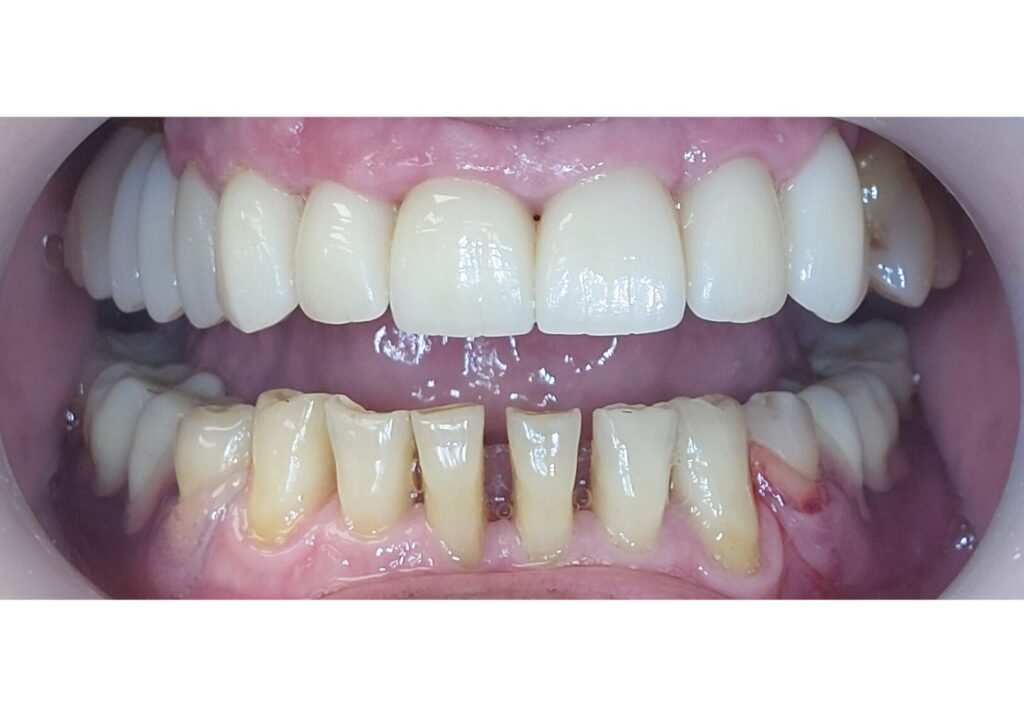

Prieš

Po

Gyd. Aušra Bieliauskienė

Abiejų žandikaulių protezavimas išimamomis plokštelėmis. Apatinio žandikaulio plokštelė - fiksuota ant lokatorių. Į kliniką kreipėsi pacientė, kuriai buvo pagamintos viršutinio ir apatinio žandikaulio pilnos išimamos plokštelės. Implantologas įsriegė 2 vnt implantų į apatinį žandikaulį apatinės plokštelės fiksacijai lokatorių sistema.

Laisvės pr. 10A, Vilnius

~ 2500 eur

Prisidėję gydytojai: Aleksandras Gordevičius